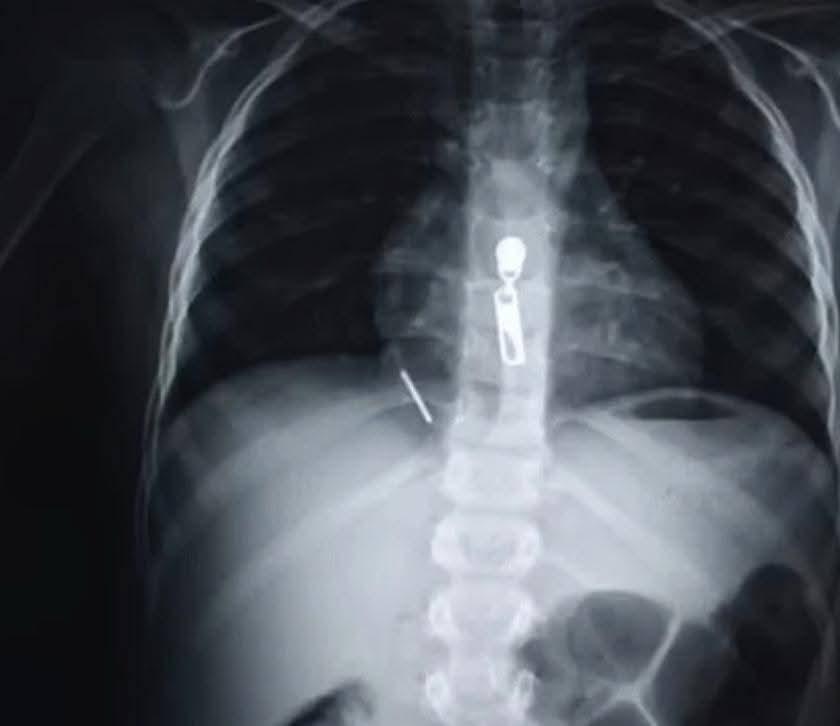

شهدت مستشفيات جامعة القاهرة (قصر العيني) إنجازاً طبياً جديداً يعكس كفاءة وتفوق "قلعة الطب" في التعامل مع الحالات النادرة والمستعصية، حيث نجح فريق طبي متخصص من قسم جراحة القلب والصدر في إنقاذ حياة طفل يبلغ من العمر 11 عاماً، حضر إلى المستشفى في حالة حرجة إثر اختراق مسمار "منجد" يبلغ طوله 5 سم لصدره واستقراره مباشرة داخل عضلة القلب، في واقعة طبية حبست الأنفاس وانتهت بانتصار جراحي مصري خالص.

بدأت تفاصيل الواقعة أثناء لهو الطفل مع أحد أصدقائه بمسدس مسامير، مما أدى إلى اندفاع المسمار ليخترق القفص الصدري ويستقر في القلب، وفور وصوله إلى مستشفى الاستقبال والطوارئ 185 برئاسة الأستاذ الدكتور أحمد ماهر مدير المستشفى، تم تفعيل بروتوكول التعامل العاجل مع الحالات الحرجة، حيث أشار الدكتور أحمد ماهر إلى أن سرعة دخول الطفل وتنسيق استدعاء جراحي القلب والصدر فور وصول الحالة كانا بمثابة حجر الزاوية في إنقاذ حياته، مؤكداً أن جاهزية غرف العمليات والطواقم الجراحية بالمستشفى تسمح بالتعامل مع مثل هذه الحوادث الجسيمة في دقائق معدودة.

وعلى الفور، تولى الفريق الجراحي بقيادة الأستاذ الدكتور حسام فتحي علي، رئيس وحدة حوادث جراحة القلب والصدر، إجراء عملية استكشاف عاجلة للصدر، حيث تبين وجود تهتك بالرئة اليمنى واختراق المسمار للغشاء التموري وإصابة القلب إصابة مباشرة تسببت في نزيف داخلي حاد حوله، وبمهارة فائقة تم استخراج المسمار وإصلاح التهتكات والسيطرة على النزيف بالكامل.